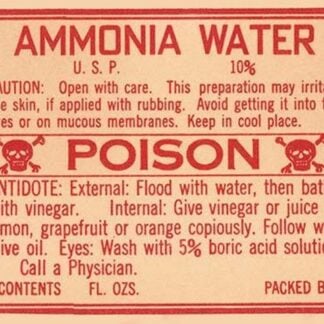

Ammonia Water

Price range: $21.99 through $285.99 Select options This product has multiple variants. The options may be chosen on the product page -